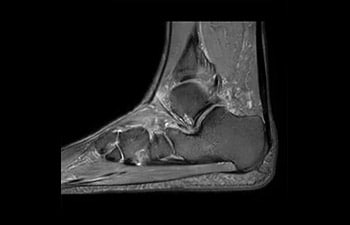

• Es una innovadora técnica de aceleración que no solo permite agilizar las secuencias, sino todo el estudio. • Implementación especial con la que las exploraciones en 2D y 3D pueden llegar a ser hasta un 50% más rápidas con una calidad de imagen prácticamente equivalente.1

• Se puede usar con todos los contrastes y con todas las regiones anatomías.